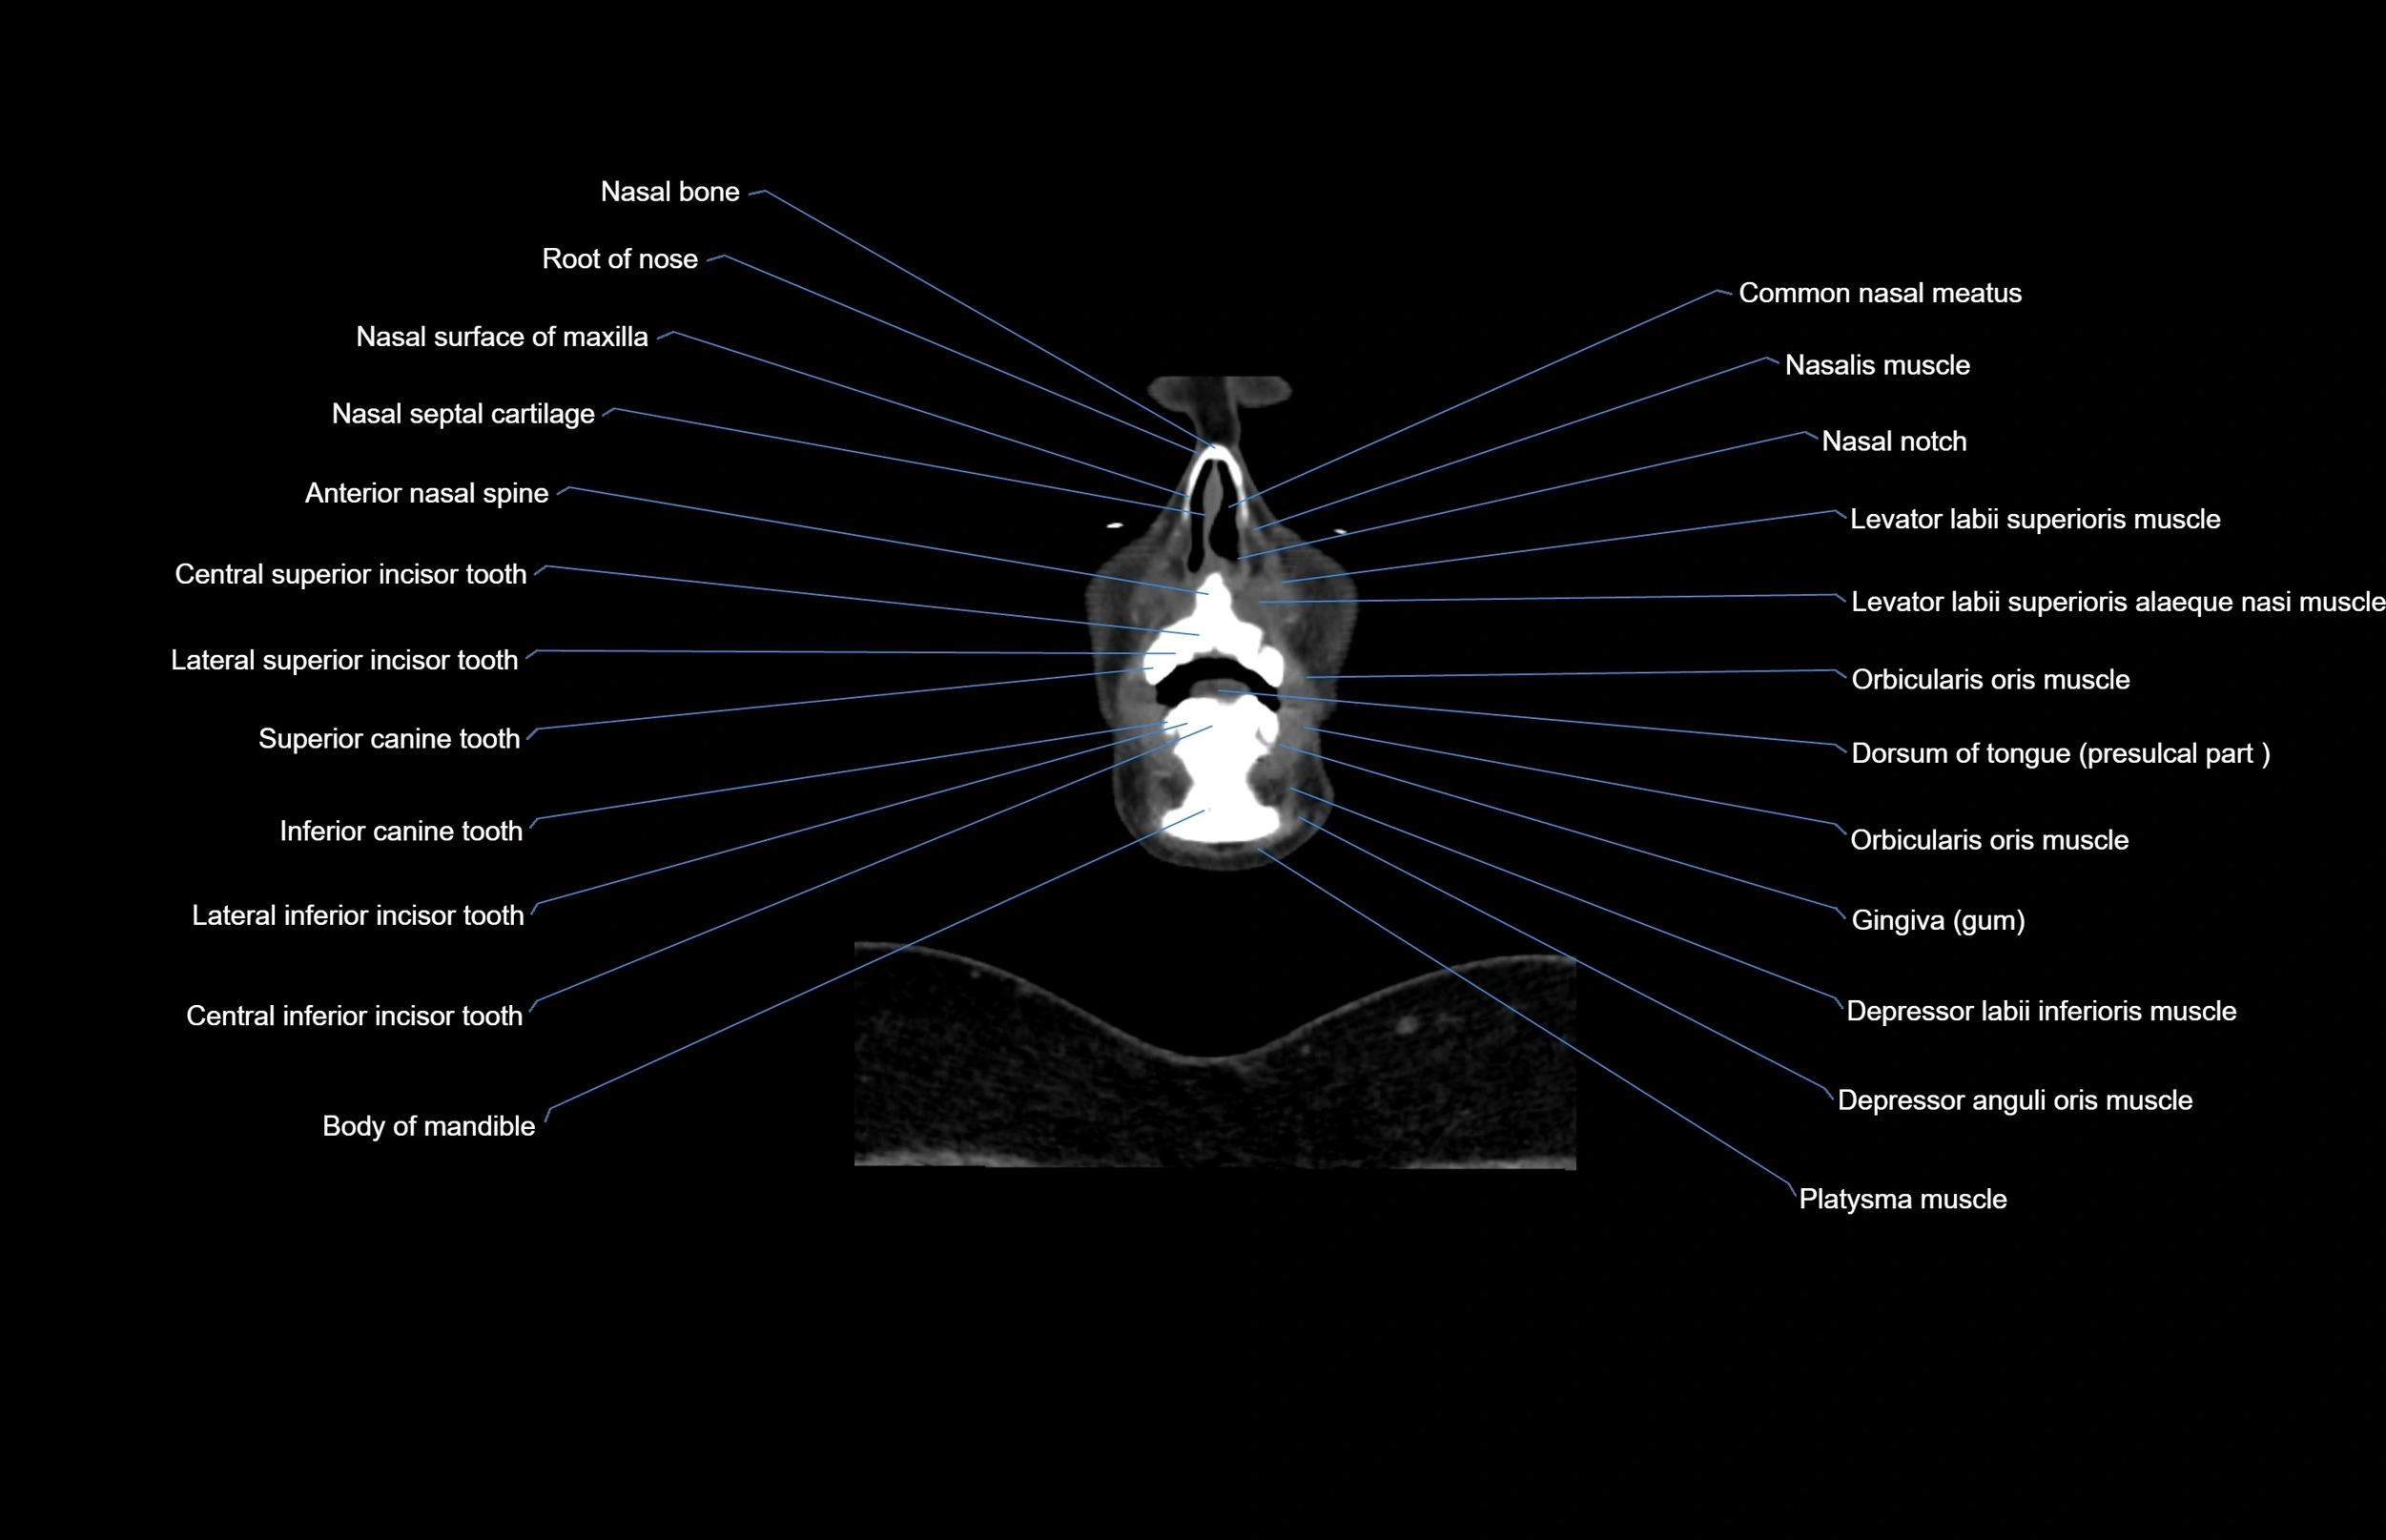

- Anterior nasal spine

- Body of mandible

- Buccinator muscle

- Central superior incisor tooth

- Common nasal meatus

- Depressor anguli oris muscle

- Depressor labii inferioris muscle

- Dorsum of tongue

- Genioglossus muscle

- Inferior canine tooth

- Lateral inferior incisor tooth

- Lateral mass of atlas

- Lateral superior incisor tooth

- Levator labii superioris alaeque nasi muscle

- Levator labii superioris muscle

- Lower lip

- Nasalis muscle

- Orbicularis oris muscle

- Platysma muscle